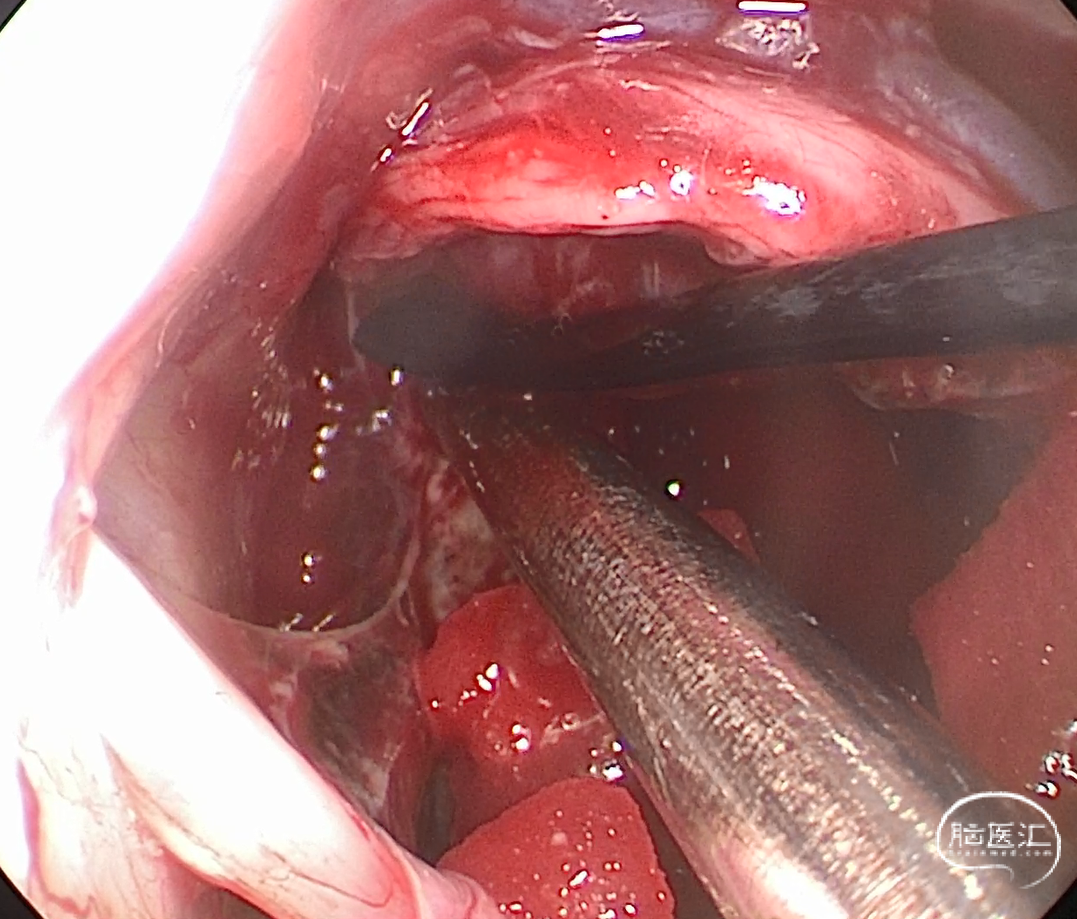

术中图片

![]()